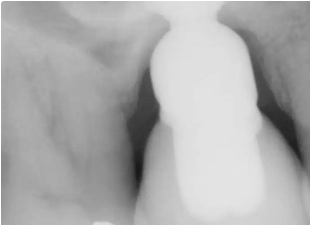

Presentamos el caso de un paciente masculino de 69 años, en el que se realizó la extracción dental seguida de la colocación de un implante Bicon SHORT® de 6,0 x 5,0 mm con pilar de elevación de seno.

El caso se restauró con una corona de pilar integrado (IAC) de 20 mm de longitud y ha sido seguido durante 84 meses.

Este caso destaca no solo por la estabilidad a largo plazo del implante corto, sino también por mostrar de forma radiográfica la aplicación de la Ley de Wolff: el hueso se adapta y se refuerza en respuesta a la carga funcional.